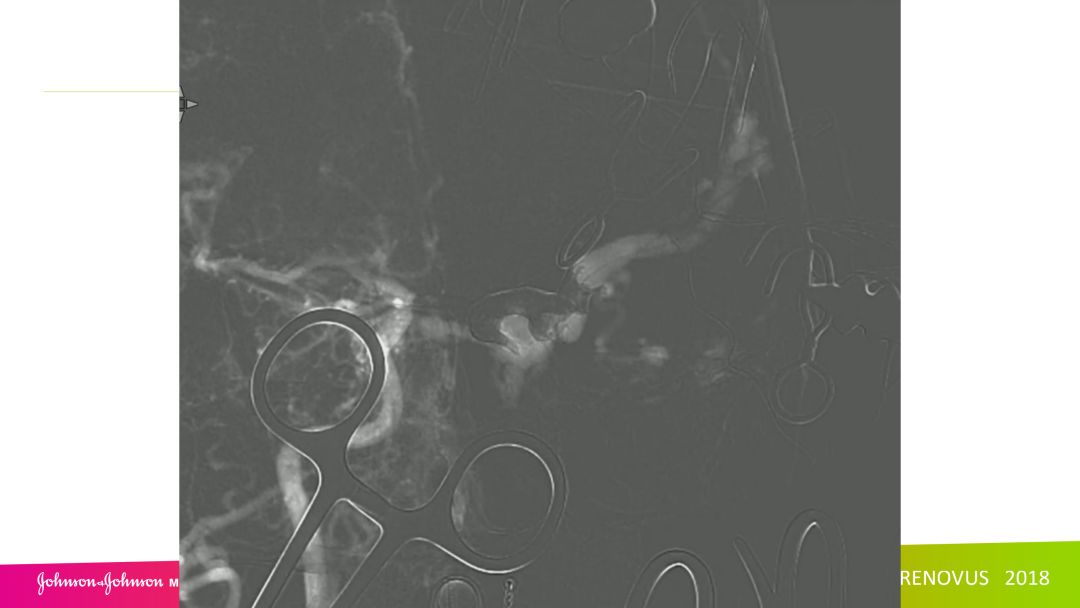

复合手术治疗海绵窦区硬脑膜动静脉瘘一例